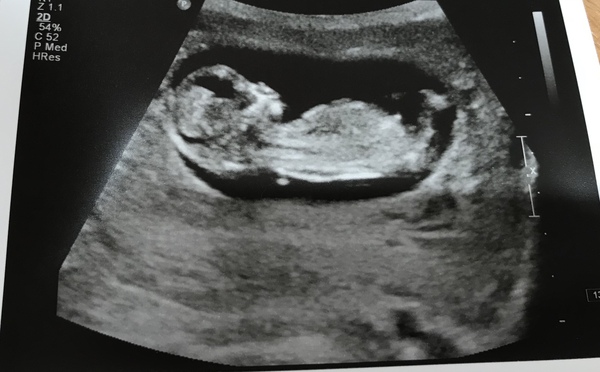

Lovely scan picture cakelaur I'm guessing girl, but I'm crap at nub theory.

Scan done today 12+5 all looks good and we had a wriggler x thinking of buying a Doppler as had a mmc at 16 weeks - which was only picked up when I went for midwife appt and she couldn’t find the heartbeat then sent for scan and no hb confirmed - so I just want to check things are ok but don’t know if it will make things worse...advice please xx